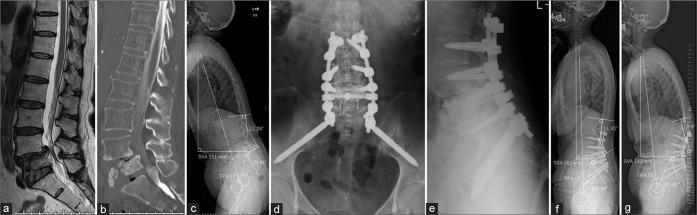

Three women, ranging in age from 69 years to 82 years, were surgically treated for a complete L5 OVBF. Two of these patients were being treated for rheumatoid arthritis. Surgery was performed using the L5 shortening osteotomy or vertebroplasty, with one- or two-level posterior lumbar interbody fusion, and posterior spinal fixation for the L2 or L3 to the pelvis. Although the spinal alignment parameters, which included lumbar lordosis (LL), pelvic incidence-lumbar lordosis, T1 pelvic angle, and sagittal vertical axis, were better as compared to that observed before the surgery, these worsened at the final follow-up due to clinical fractures that occurred at the adjacent vertebral body and proximal junctional kyphosis. Compared to preoperative Japanese Orthopaedic Association (JOA) scores, postoperative JOA scores were improved and maintained at the final follow-up.

三名年龄在69岁至82岁之间的女性接受了L5 OVBF的手术治疗。其中两名患者正在接受类风湿性关节炎治疗。手术采用L5缩短截骨术或椎体成形术,同时进行一或两节段的后路腰椎椎间融合术,并对L2或L3至骨盆进行后路脊柱固定。尽管包括腰椎前凸(LL)、骨盆入射角-腰椎前凸、T1骨盆角和矢状垂直轴在内的脊柱对线参数在术后较术前有所改善,但由于相邻椎体发生临床骨折和近端交界性后凸,这些参数在末次随访时恶化。与术前日本骨科协会(JOA)评分相比,术后JOA评分有所改善,并在末次随访时得以维持。